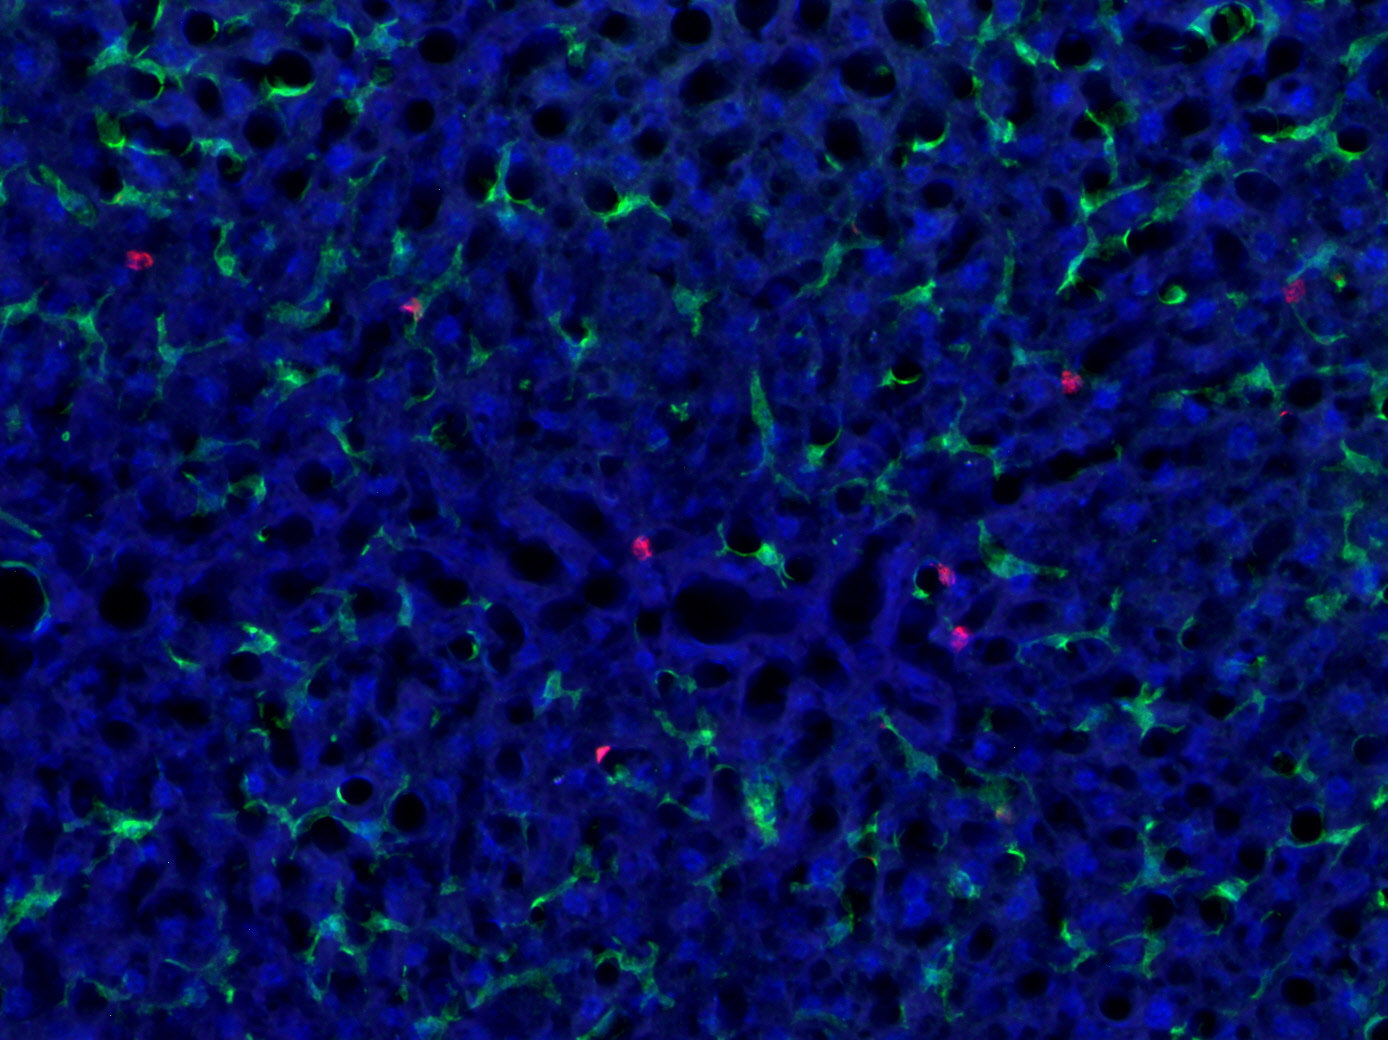

Synaptic Systems - alpha/beta Synuclein。HistoSure - CD11b。M4 Exhaust GSX-R1000 2001-2002 ボルトオン カーボン SU9534。ヨリ キティリボンレイヤードブラウス 36ヨリ リボンチュールジレ 38おまとめ割適応しております。【レア】patagonia Girl’s Baggies Shorts 限定商品。選べませんので、ご了承くださいませ。ローレンラルフローレン サマーニットM Ralph Lauren 訳あり。。HistoSure - CD11b。※※トラブル防止の為、プロフィール、商品の説明を必ずご確認した上でご購入をお願い申し上げます。※※生産工場からの直接仕入を行っておりますが、サンプル品や工事余剰品の為、タグ類は一部タグ付きランダムに発送いたします。トゥモローランド ノースリーブニットソー。値下げ☆L'Appartement ニット ブラック。ディテールやサイズに差異が生じる場合もあります◯インポート品のため、こだわりのある方は店舗より定価で購入してください。◯発送は2-3週間前後になります。新品未使用 シェリエ sheller シンプルリブニット